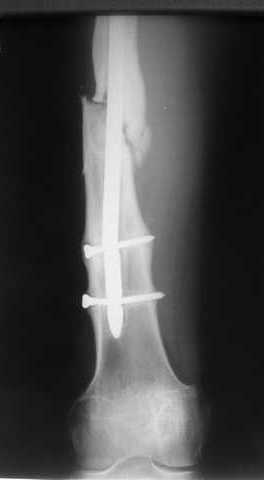

В приложении пример, как их использовали после остеотомии бедра по поводу сросшегося с вальгусом перелома, чтобы не дать гвоздю уйти во внутренний мыщелок.

Да, действительно красивый клинический пример: виден вальгус до операции и последующая коррекция углового смещения на "полярах". Я так понимаю, что в вашей клинике есть возможность использовать различные фиксаторы. Почему не использовали DFN? Спицы какие используете? Киршнера или Илизаровские? С виду очень тонкие...